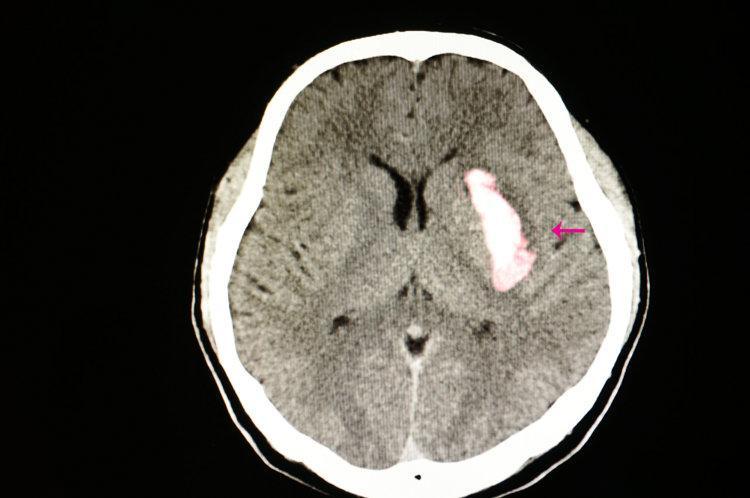

正是他服用的阿司匹林,導致了嚴重的胃出血,在這個過程中,吳大爺犯了兩個致命錯誤,一個是他本身就患有胃潰瘍毛病,濫用阿司匹林會有出血風險;另一個是他本身並沒有心血管疾病,也沒有經過醫生評估,就自行服用阿司匹林預防心血管疾病。

一、長期服用阿司匹林會導致胃出血、腦出血?

因其一方面可以抑制血小板聚集,降低動脈硬化發展的進程,另外一方面也會增加出血事件,尤其是腦出血、胃腸道出血風險。

《JACC》上發表過一項涉及16項合計有17.1萬餘人研究的薈萃分析,經分析發現,相較於服用安慰劑的受試者,阿司匹林用於心腦血管疾病的一級預防,可讓心梗風險下降15%,但同時會增加48%的大出血風險